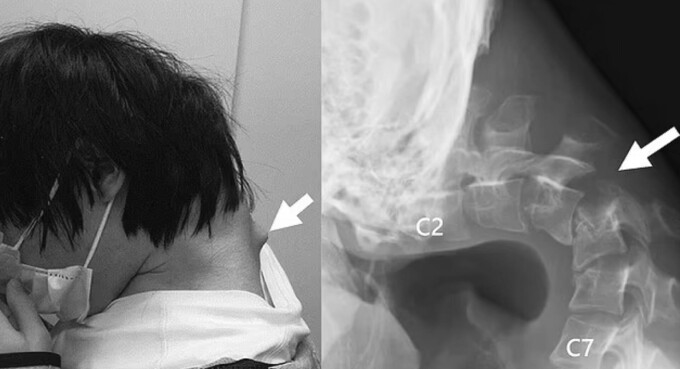

Tratamentul a început cu utilizarea unui guler cervical, menit să stabilizeze capul. Totuși, pacientul a acuzat amorțeli, astfel că medicii au decis să intervină chirurgical. Au fost îndepărtate porțiuni din vertebrele afectate, precum și țesutul fibros apărut în urma inflamației cronice. Ulterior, au fost montate tije și șuruburi metalice pentru a realinia gâtul.

Rezultatele au fost pozitive: la șase luni de la operație, pacientul își putea ține capul în poziție normală, iar după un an, simptomele de disfuncție au dispărut complet.

Tânărul de 25 de ani se confruntă cu dureri cumplite / Sursa foto - www.sciencedirect.com